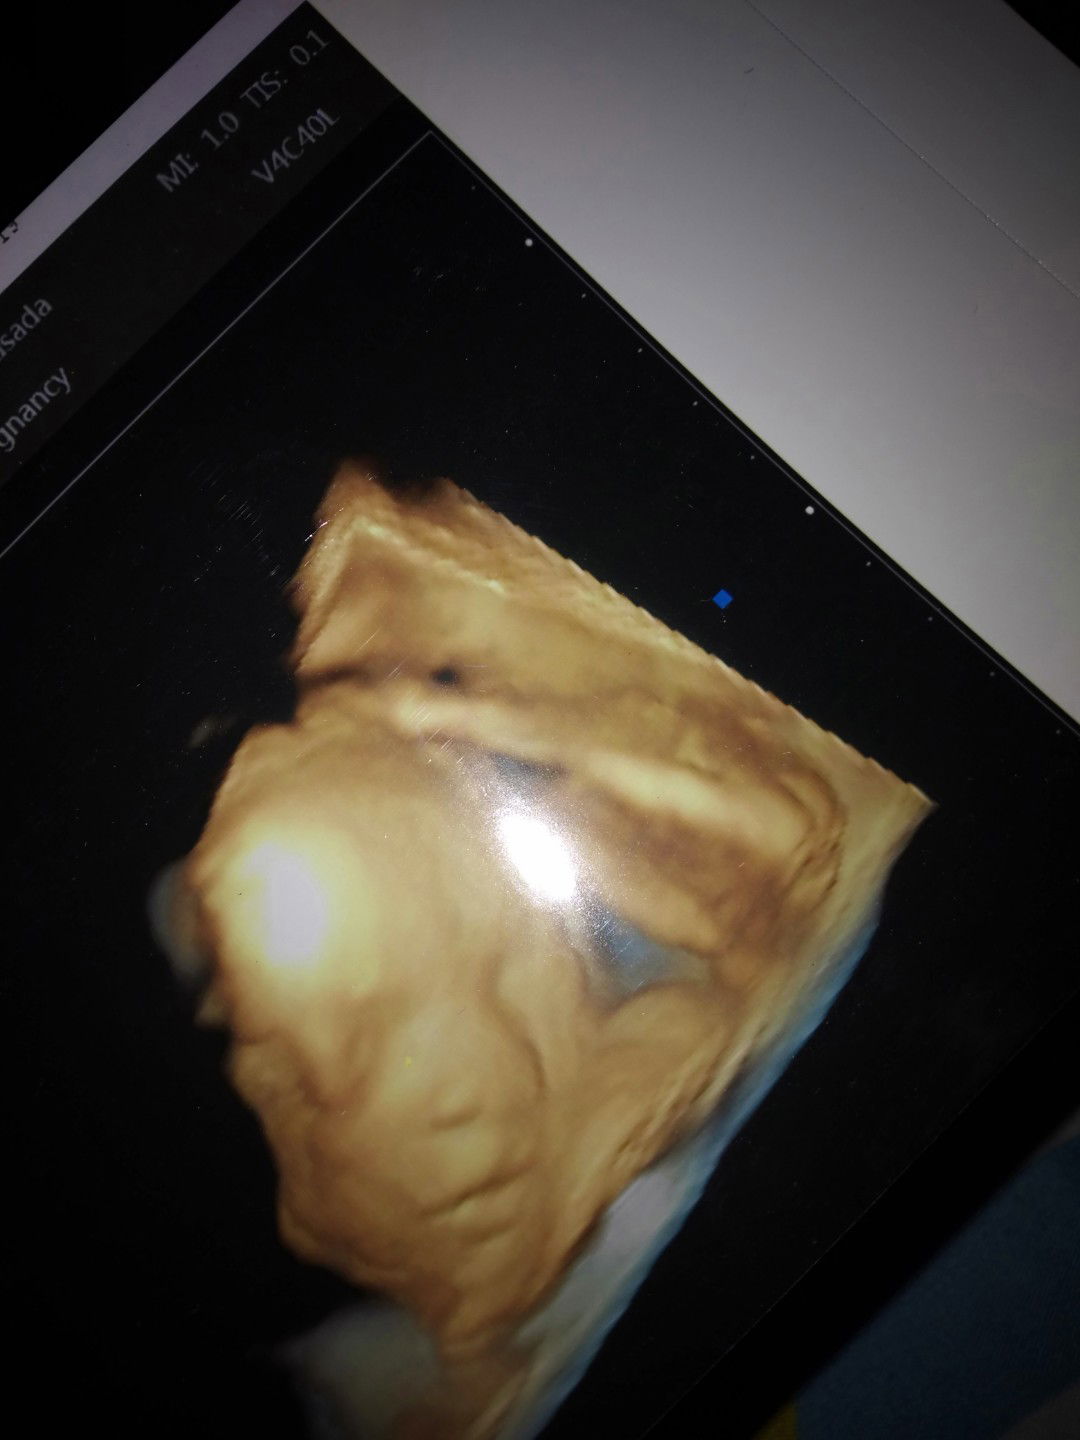

Mana foto usg anak bunda

Ini jagoanku mana jagoan bunda2 yg lain nih idung anak ku kaya ayah nya Masyaalloh Tabarakallah????

26 Week 1 hari